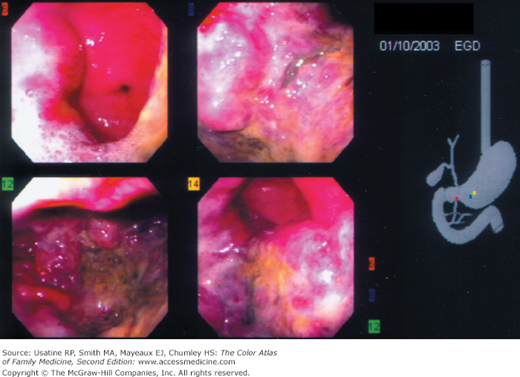

A 72-year-old Japanese immigrant was brought in by his family with complaints of difficulty in eating, vague abdominal pain, and weight loss. Endoscopy and biopsy confirmed gastric adenocarcinoma (Figure 60-1). Liver metastases were found on abdominal CT. The family and the patient chose only comfort measures and the patient died 6 months later.

- Diagnosis can be made on endoscopy (Figures 60-1 and 60-2) with biopsy of suspicious lesions. Confocal laser endomicroscopy may improve detection of early lesions.12